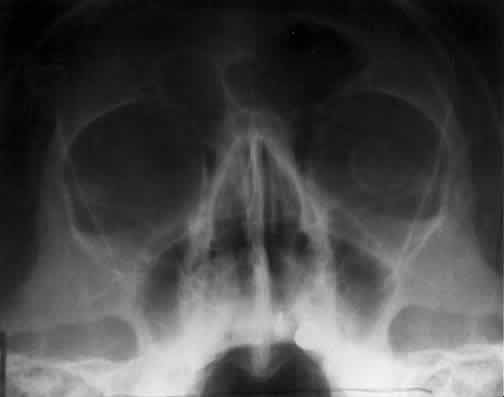

CALDWELL PROJECTION

In 1918 the evaluation of the frontal and ethmoid sinuses prompted Caldwell9 to describe a projection (Fig. 3) that eliminates the superimposition of the sphenoid bone on these paranasal sinuses. The patient is positioned with both the nose and forehead against the x-ray cassette while the x-ray beam is directed downward 15 degrees to 23 degrees to the canthomeatal line.5,6,9 This orientation also projects the petrous bones inferior to the orbit, thus avoiding obscuration of the orbital structures. As in the Waters view, the Caldwell view is a posterior-anterior projection. This excellent view of the frontal and ethmoid sinuses also allows good visualization of the orbital rims, greater and lesser sphenoid wings, lacrimal gland fossa, medial orbital wall, and both the superior and inferior orbital fissures.10 The innominate line is prominent in this view and represents the depression on the temporal surface of the greater wing of the sphenoid bone where it forms the medial wall of the temporal fossa or lateral wall of the orbit. This innominate line can be straight, end with a medial right angle turn, or continue inferiorly to form the outline of the pterygoid plate.8 A lack of continuity of the innominate line suggests a fracture of the lateral orbital wall.

Fig. 3. A. Schematic showing positioning for a Caldwell projection. (CM, canthomeatal line; CR, central ray) B. Radiograph of a Caldwell projection. The petrous ridge is positioned at the orbital floor. Detail of the orbital floor and maxillary sinus is blocked. C. The radiograph is taken at a steeper angle so the petrous ridge is now positioned lower within the maxillary antrum. (a, frontal sinus; b, innominate line; c, inferior orbital rim; d, posterior orbital floor; e, superior orbital fissure; f, greater wing of sphenoid;g, ethmoid sinus; h, medial orbital wall; i, petrous ridge; j, zygomatic-frontal suture; k, foramen rotundum) (A; Rao VM, Gonzalez CF: Plain film radiography and polytomography of the orbit. In Gonzalez CF, Becker MH, Flanagan JC [eds]: Diagnostic Imaging in Ophthalmology, pp 1–7. New York, Springer Verlag, 1986)